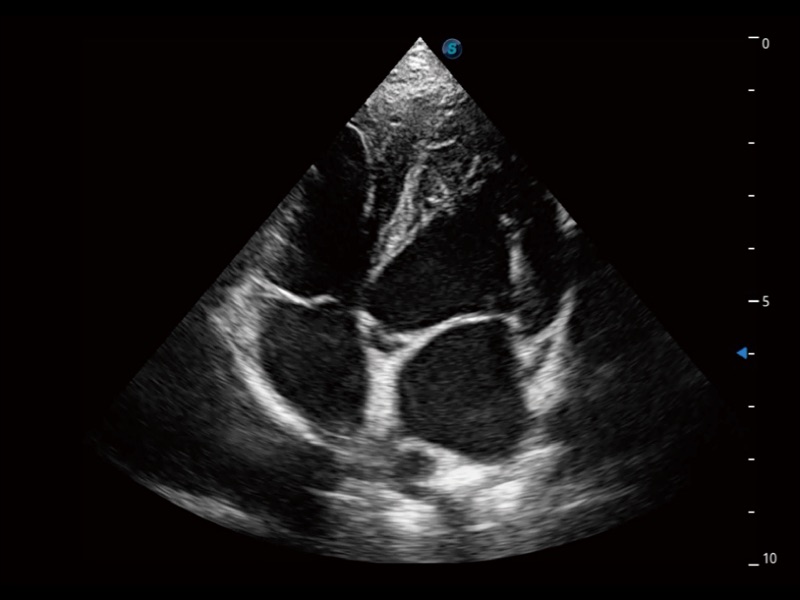

猫、中小型犬及小型异宠动物

ProPet 70 进一步提升了微米成像算法,更加注重对基础原始图像的还原和保留,在有效减少斑点噪声、增强组织边界显示的同时,避免过度优化丟失真实的解剖信息。

ProPet 70专为动物医生设计,对不同的动物体型和生理结构作出了针对性的优化。通过动物影像专用软件,可满足个性化的应用需求,帮助动物医生获得更精确的诊断数据。

为精细结构及组织边缘提供高清晰度的图像和更大的成像视野。帮助减轻医生的用眼疲劳,快速精准获得测量的数据。